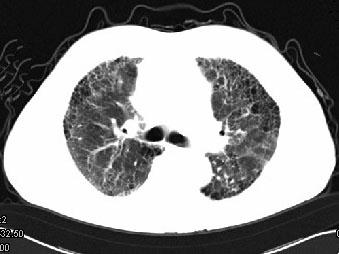

问题 男,68岁,咳嗽,气喘10年,桶状胸,CT如图,最可能的诊断为 ( )

选项 A.双肺结核 B.慢性支气管炎 C.支气管扩张 D.肺间质性病变 E.支气管囊肿

答案 D